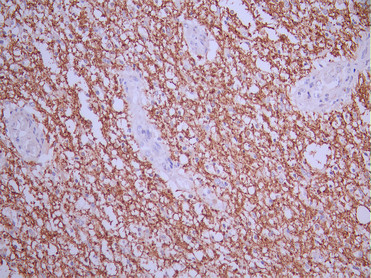

IHC image of CSB-RA061500A0HU diluted at 1:100 and staining in paraffin-embedded human glioma cancer performed on a Leica BondTM system. After dewaxing and hydration, antigen retrieval was mediated by high pressure in a citrate buffer (pH 6.0). Section was blocked with 10% normal goat serum 30min at RT. Then primary antibody (1% BSA) was incubated at 4°C overnight. The primary is detected by a Goat anti-rabbit polymer IgG labeled by HRP and visualized using 0.05% DAB.